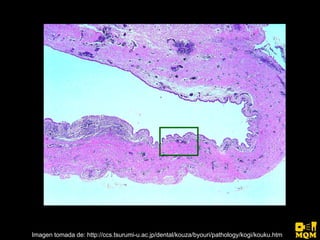

El quiste nasopalatino es un quiste embrionario situado en la línea media en la parte anterior del paladar, que se origina de los restos del conducto nasopalatino. Generalmente aparece entre los 40-60 años y se presenta como un aumento de volumen blando y no doloroso entre los incisivos centrales superiores que puede causar divergencia radicular. Las características radiográficas incluyen una lesión radiolúcida, bien delimitada y de forma redondeada u ovalada que cruza la línea media maxilar.